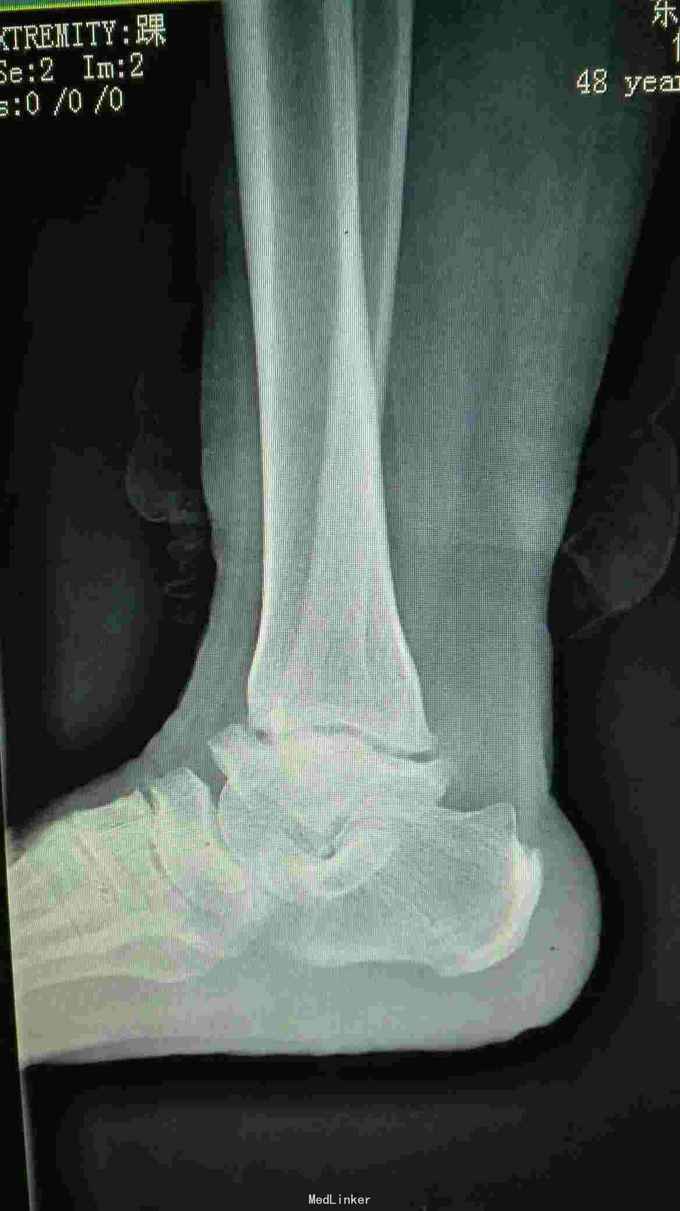

病人骑电动车摔倒,右脚踝扭伤,来院就诊。现在感觉疼痛加重。以往有疼痛感2年,自己感觉脚踝相对别人较粗,并偶有活动受限。在东北生活10年。

拍右踝关节正侧位片:1.未见明显外伤性改变 2.考虑大骨节病

诊断:1.右踝关节软组织损伤 2.大骨节病 治疗:嘱病人少活动,多休息,必要时将患侧腿抬高,先用冷毛巾冰敷1日。再配合消肿止痛药物治疗。